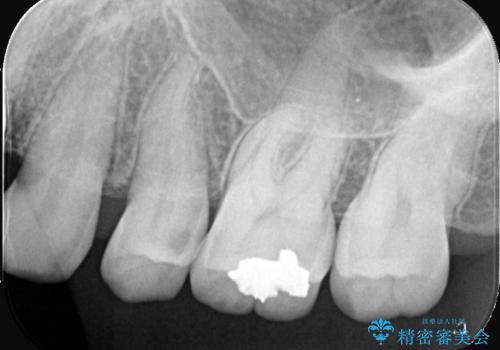

左上5番目の歯の側面に実質欠損を認め、隣の6番目の歯にも虫歯を認めたため両歯ともセラミックインレーでの治療となりました。

左上5番遠心に実質欠損を認め、さらに5番と6番の隣接面にもカリエスを認めました。6番の咬合面には、元々コンポジットレジン修復が施されており、劣化がみられたのでその部分も含め修復することとなりました。